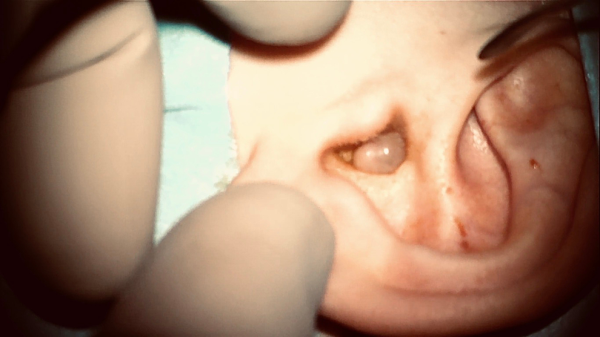

Figure 1

Otomicroscopy showing preoperative finding of a smooth, slightly translucent, oval-spherical tumor with a diameter of 1 cm, filling the left external auditory canal.